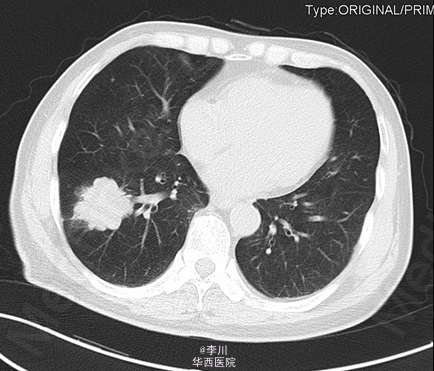

患者男,73岁,因“咳痰伴痰中带血2+月”入院。患者于2+月前无明显诱因出现咳痰伴痰中带血,无咳嗽、胸闷、胸痛等症状,未予以处理。10+天前于外院就诊,行胸部CT、心脏超声、纤支镜等检查示:右肺占位。予以口服及输液治疗13天(具体不详),症状无明显好转。

于全麻下行“VATS右肺下叶切除术+淋巴结清扫术”,术中见:肿块块位于右肺下叶,约4.2*3.9cm大小,脏层胸膜皱缩、无侵犯壁层胸膜;术中冰冻结果:(右下肺肿块)腺癌。

肺癌的分叶征是周围型小肺癌最常见的基本征象。其病理基础一是与肿瘤边缘各部位肿瘤细胞分化程度不一,生长速度不同有关;二是肺的结缔组织间隔,进入肿瘤的血管、支气管分支、从肿瘤内向外生长的血管和结缔组织等引起肿瘤生长受限并产生凹陷,从而形成分叶的形态。分叶征对于鉴别肺部包块良恶性具有重要价值。